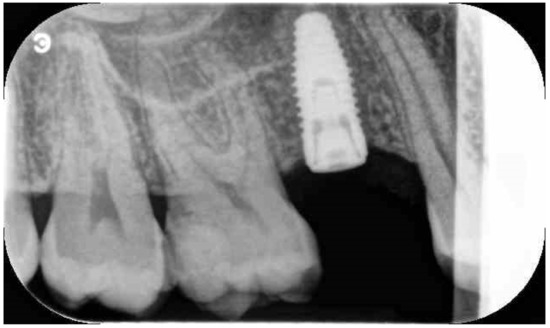

Implant Placement Following Crestal Sinus Lift with Sequential Drills and Osteotomes: Five Years after Final Loading Results from a Retrospective Study

3. Results

| Survival rate | 98.1% | 98.1% |

| Complications | BOP at 2 implants | None |

| Marginal Bone loss | 0.94 ± 0.18 mm | 1.24 ± 0.28 mm |

| Table 2 | Implant Survival Rate | MBL | Follow-Up |

|---|---|---|---|

| Chen e Cha et al., 2005 | 99.3% | Not reported | 8 years |

| Tallarico et al., 2017 | 100% | 0.19 ± 1.05 mm | 1 year |

| Xhanari et al., 2019 | 100% | 0.99 ± 0.55 mm | 1 year |

| Gatti et al., 2018 | 100% | 0.33 ± 0.24 mm | 2 years |

| Lumbau et al., 2020 | 98.1% | 1.24 ± 0.28 mm | 5 years |